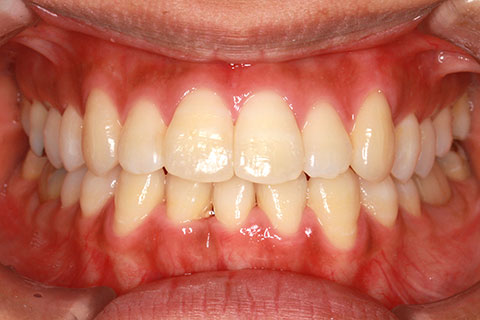

治療前

治療中

治療後

- 年齢・性別

- 23歳女性

- 治療期間

- 1年6ヶ月

- 抜歯

- 上顎4番

- 治療費

- 110万円(税込み)

- 備考

- ハーフリンガル矯正

- 治療内容

- 上下前歯部凸凹の改善

- 施術の副作用(リスク)

- 裏側矯正の特性上、表側矯正と比較すると治療期間が長くかかる場合が多い。